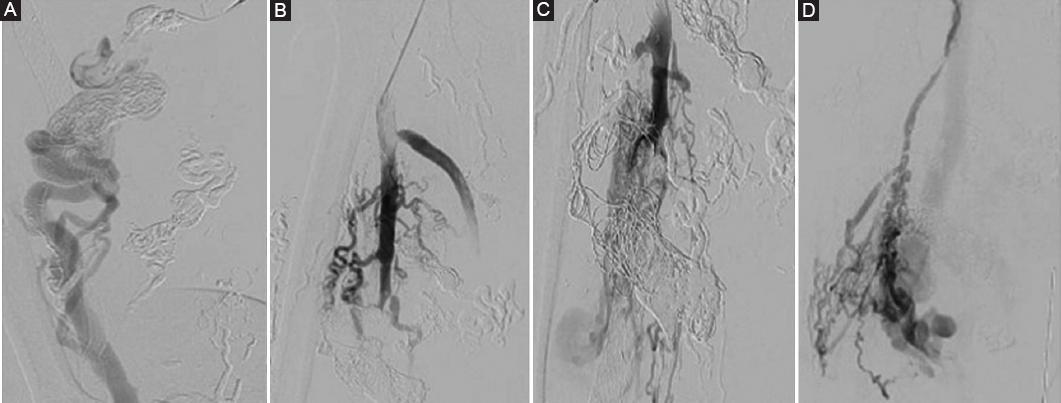

The CTA findings were then confirmed in the first endovascular session with the angiography, which also detailed multiple feeding vessels from the profunda femoris and superficial femoral artery. AVM was classified as a type IIIb according to the angiographic classification4, with multiple shunts between arterioles and venules and dilation of the fistulae. In the first endovascular intervention, feeding arteries embolization was made through a cross-over arterial left femoral access with selective catheter placement in the feeding vessels and then five Onyx-34 embolizations were made, final arteriography showed presence of multiple arteriovenous fistulae (Fig. 2A). In the second session, the left femoral puncture was done and a cross-over was made again with selective embolization with Onyx-34 of the hypogastric feeding vessels and selective embolization of right common femoral feeding vessels was done and five coils were used (Fig. 2B). In the third session, a direct puncture in the right femoral artery, then a selective feeding arteries embolization with Onyx-34 and eleven coils to the common and superficial femoral feeding vessels was done (Fig. 3A), together with direct US-guided puncture of the venous dilated veins. In the fourth and fifth sessions, an embolization with Onyx-34 and six coils both to superficial femoral feeding vessels and dilated superficial veins was done (Figs. 3B and C).

Figure 2 Final angiography after first embolization session with Onyx 34. A: multiple feeding vessels from the profunda femoris and superficial femoral artery. B: control angiography after second session with selective afferences embolization with Onyx-34 and five coils.